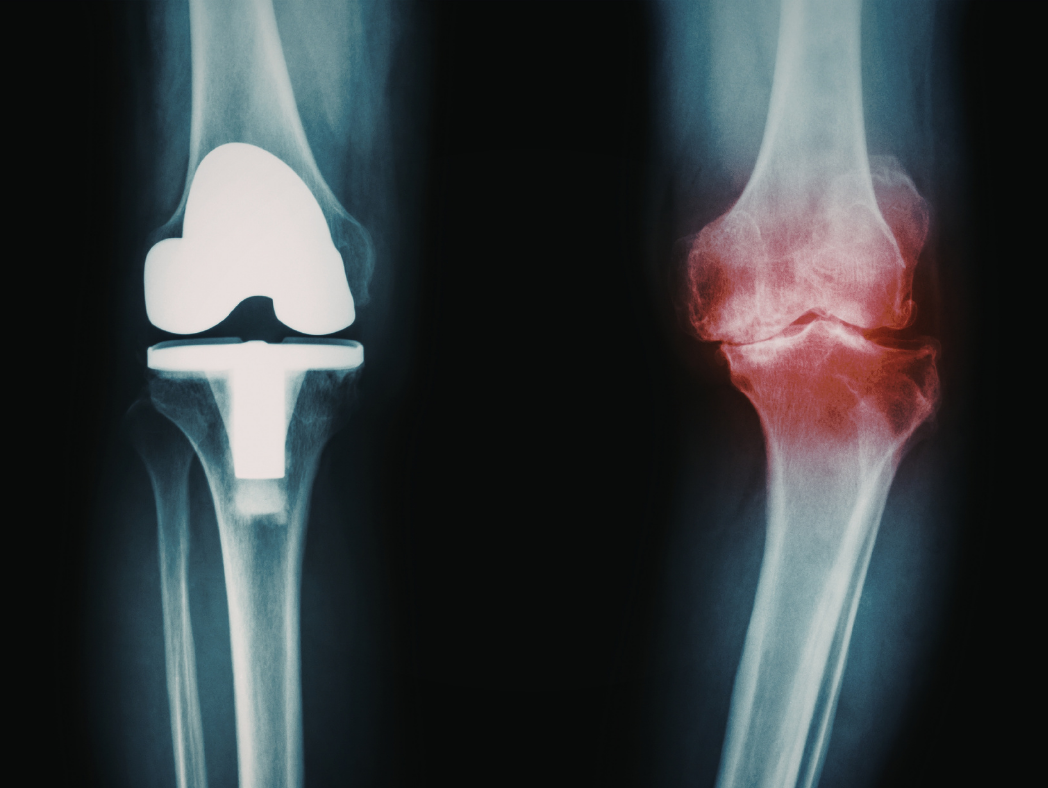

Featured Image

Artrose (slitasjegikt): slik kan du dempe smerter naturlig og bremse utviklingen